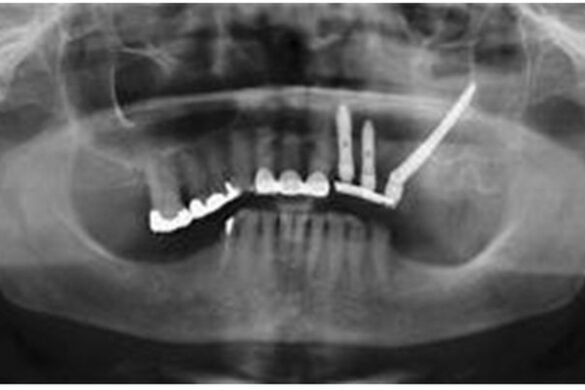

Zygomatic dental implants are longer than traditional dental implants, reaching the dense zygomatic bone located in the upper jaw. They provide a secure anchoring point for dental restorations like dentures or bridges.

This unique approach eliminates the need for bone grafting, making it a viable option for patients with substantial bone loss. Compared to traditional dental implants, zygomatic implants are particularly advantageous in cases where the patient lacks adequate bone density for conventional implants.

Traditional implants typically require a certain amount of healthy bone for successful placement, whereas zygomatic implants overcome this limitation. Zygomatic dental implants are typically recommended for individuals who have experienced significant bone loss, making traditional implants unsuitable.